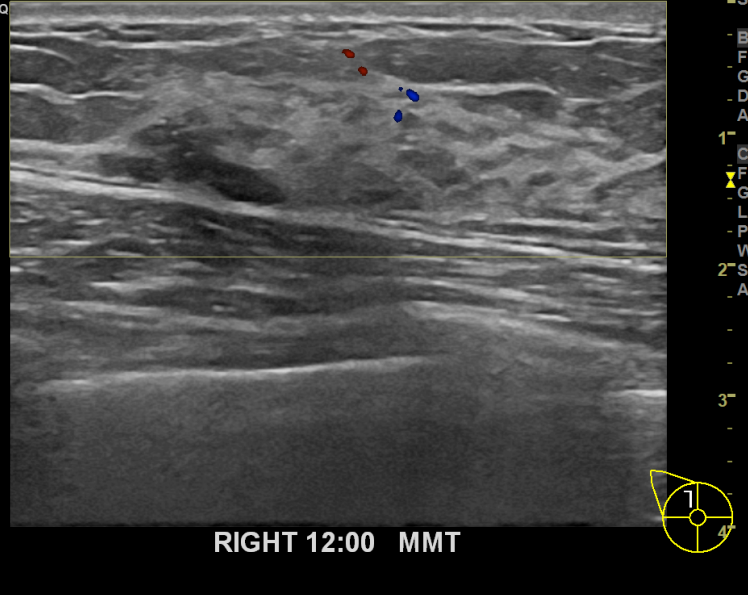

상기환자 외부병원에서 우측12시방향 조직검사한 후 양성나왔던 혹

본원에서 추적관찰 중 모양변하고 커져 맘모톰시행하였습니다.

그 결과 유방암진단되어 상급병원의뢰드렸습니다.